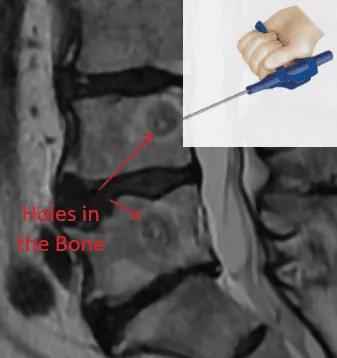

MRI of spinal vertebrae with labeled bone holes and a tool illustration in the top right corner.

Step 4: RF Probe Burns Bone Marrow & Nerves

A radiofrequency probe is inserted to burn and destroy the vertebral body bone marrow and nerves within.